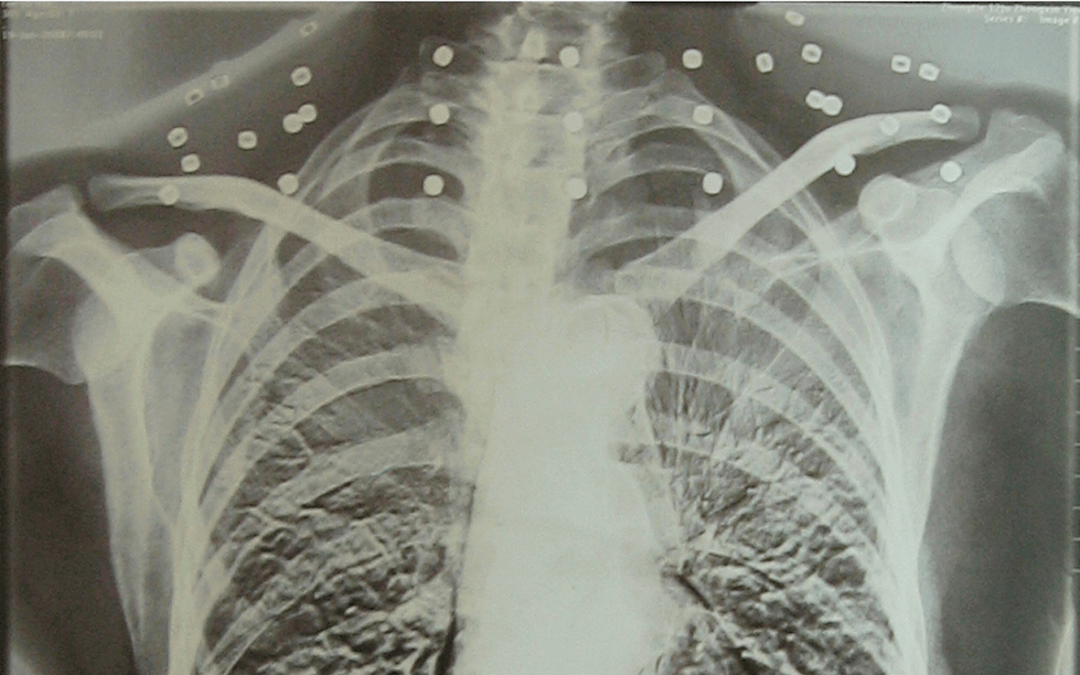

这张照片

是今年82岁的吴以先老人

拍摄的一张CT照

但实际上是

吴以先的颈部和腹部

共分布着33枚弹片

他体内的弹片都没有取出

每到天气变化时

身体留有弹片的位置就有痛感

但吴以先不考虑取出弹片

在他看来

这是他与战友并肩作战的见证

是他的勋章